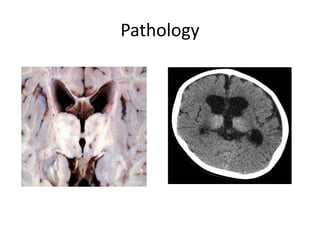

Pathology